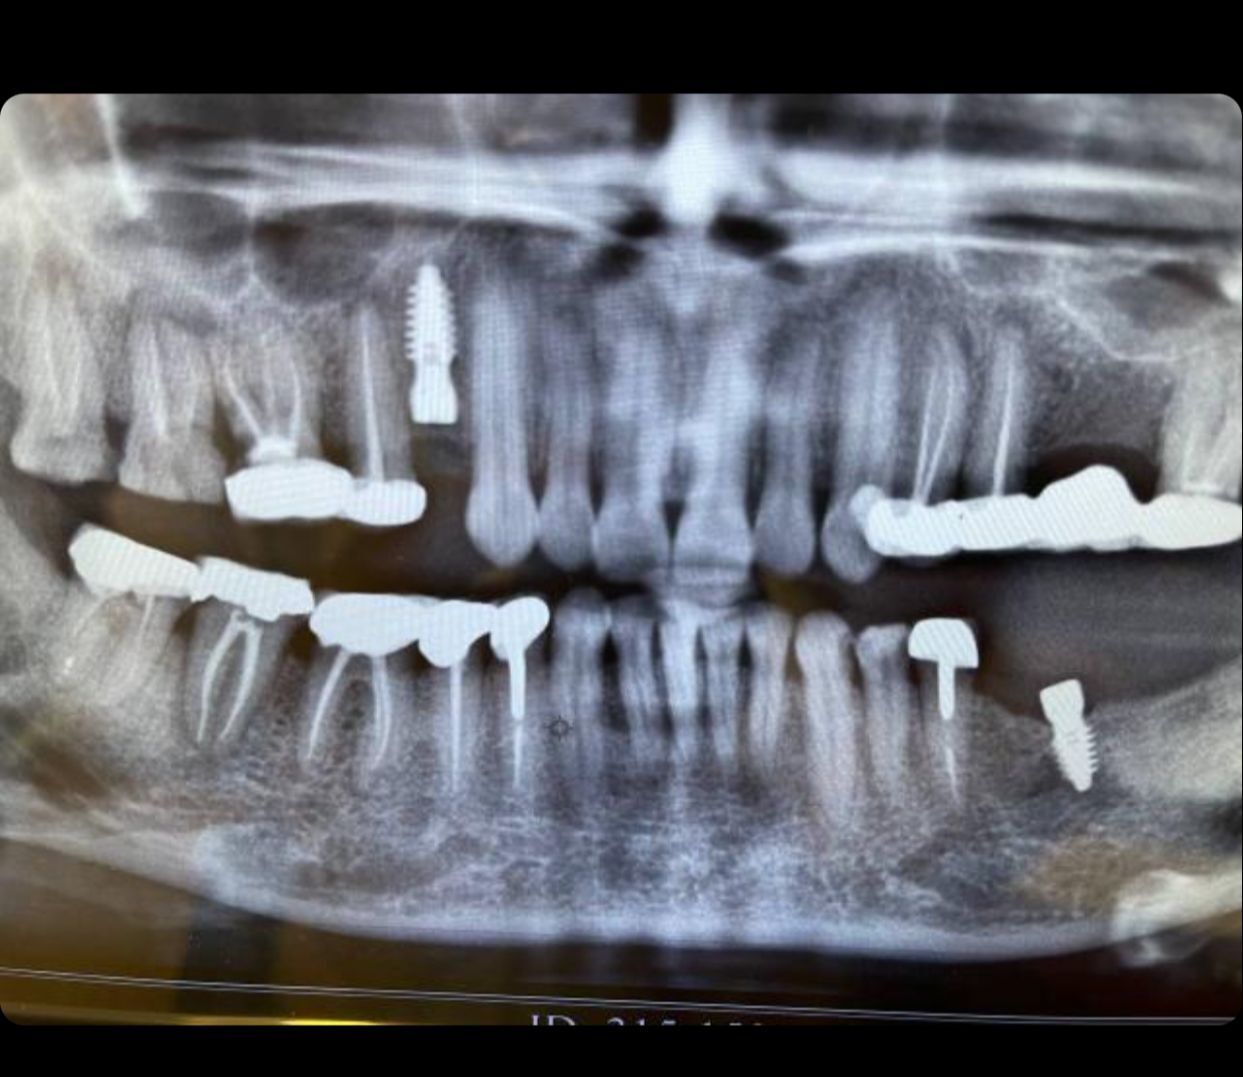

Dental Implants

A dental implant is a root of an artificial tooth. It is fixed into the jawbone and so it can facilitate permanent artificial teeth. Dental implants can support a single artificial tooth or multiple artificial teeth. They are made of dental material like titanium or zirconium. Unlike dentures or other dental restorations like dental bridges, artificial teeth fixed on top of dental implants are closest to natural teeth. They provide superior functionality enabling chewing of food and clear speech. Dental implants are fixed into the jawbone with a dental surgery. Once dental implants are firmly fixed, artificial teeth, dentures, or crowns are placed.

Sinus Lift Surgery

In order to successfully place dental implants you need sufficient bone. In certain situations dentist need to perform specific procedures in order to create bone volume. One such procedure is sinus lift. The maxillary sinuses are empty rooms that have nothing at all in them. When upper teeth are removed, there is often just a thin wall of bone separating the maxillary sinus and the mouth. Dental implants need bone to hold them in place so when the sinus wall is very thin, it is impossible to place dental implants in this bone. There is a solution called a sinus graft or sinus lift graft. The dental implant surgeon enters the sinus and sinus membrane is then lifted upward and donor bone is inserted into the floor of the sinus. After several months of healing, the bone becomes part of the patient’s jaw and dental implants can be inserted and stabilised in this new sinus bone. The sinus graft makes it possible for many patients to have dental implants when years ago there was no other option other than wearing loose denture.